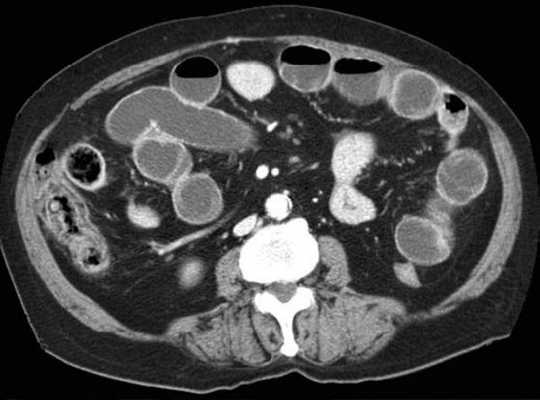

(Слева) На аксиальной КТ, выполненной женщине 4 7 лет с жалобами на боль, определяется, что верхняя брыжеечная артерия и вена находятся в положении, обратном типичному, а тонкая кишка целиком расположена в брюшной полости с правой стороны. Определяется утолщение стенки тощей кишки и ограниченный асцит, а также расширение просвета кишки.

(Справа) На аксиальной КТ с контрастным усилением у этой же пациентки визуализируются другие сегменты тощей кишки с утолщенной стенкой. Мальротация подтвердилась на операции наряду с ишемическими изменениями тощей кишки, которая была пережата из-за спаек.